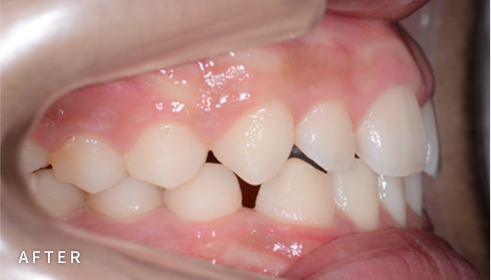

PROGRAM 02

비발치 덧니 교정

덧니고민, 비발치로 교정하세요

악궁 확장, 미니 스크류, 치간 삭제 등 다양한 방법을 활용해 가능한 한

발치를 피하고, 자연스럽고 만족스러운 결과를 얻을 수 있도록

정밀하게 계획하고 진료합니다. 발치 여부가 애매한 경우,

‘레벨링 후 재평가’ 과정을 거쳐 비발치를 우선 고려합니다.